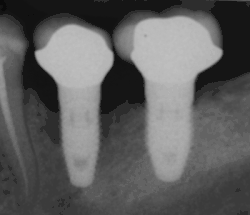

Bone loss (peri-implantitis) on implants over 7 years in a heavy smoker

Fixture show